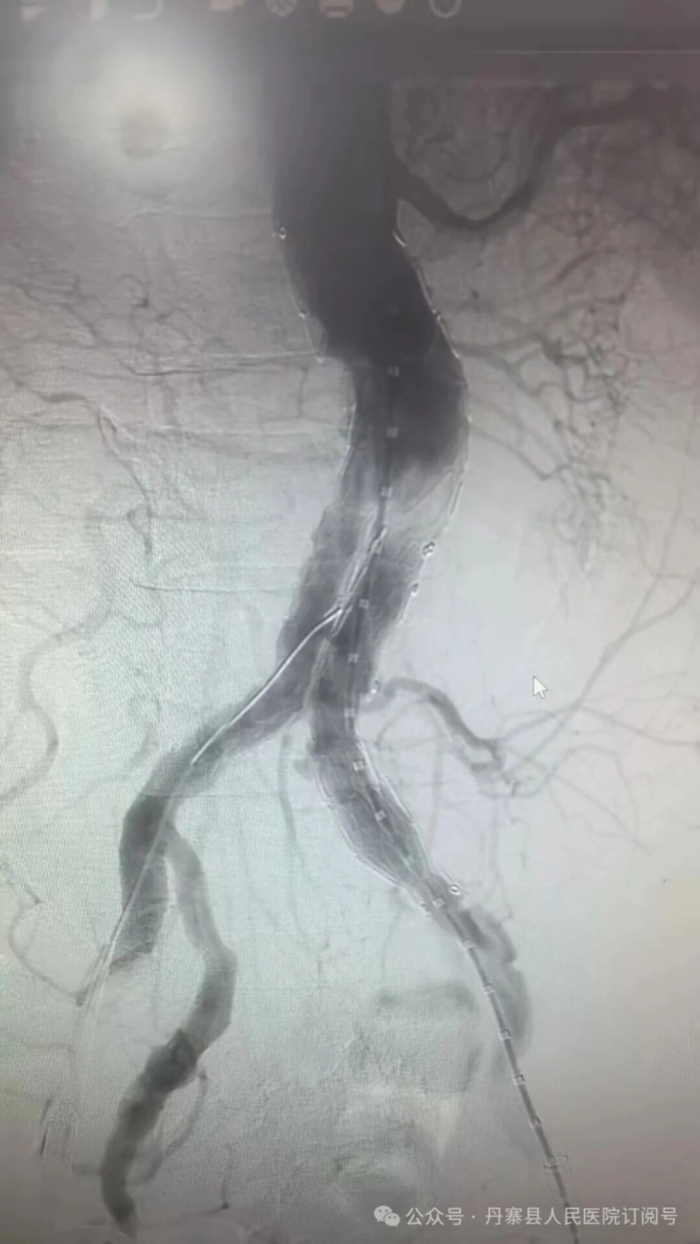

在广东省中西医结合医院专家的现场指导下,该院介入肿瘤科团队为一位病情复杂的“腹主动脉穿透性溃疡合并壁间血肿”患者,施行了“腹主动脉覆膜支架腔内隔绝术”。这项技术通过患者双侧大腿处的微小穿刺点,将覆膜支架精准输送至病变血管部位,完成从血管内部的“修复”,避免了传统开放手术的创伤。